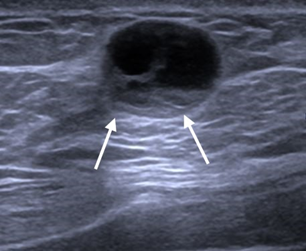

Figure 1 Ultrasound image of the right breast showing a mixed solid cystic lesion with microlobulated border at the retro-areolar region.